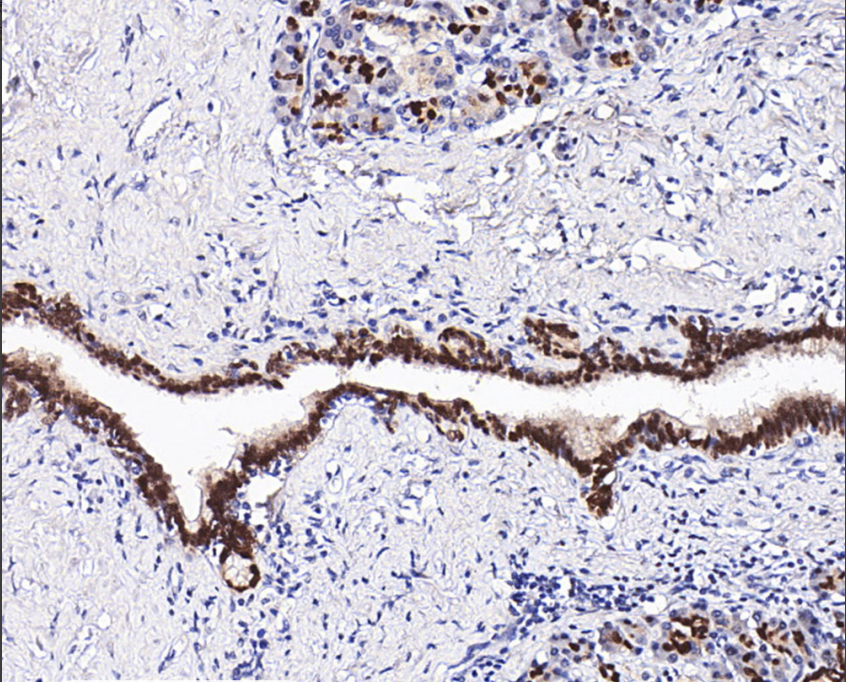

Cellular localization: nucleus

Positive control: breast/colon cancer

Antigen repair: heat repair (citric acid)

SOX9 is a transcription factor associated with SRY (sex-determining region of the Y chromosome), which affects sex determination and differentiation, participates in the development of bone, nervous system and pancreas, and is associated with the development of tumors.Mutations or deletions in the SOX9 gene are one of the most important causes of a variety of skeletal diseases in humans and undergoes sex reversal. According to the literature, the expression level of SOX9 in general chondrosarcoma is significantly higher than that in normal cartilage tissues, and it is expressed at a low level in dedifferentiated chondrosarcoma; SOX9 is highly expressed in a variety of tumors, such as prostate, gastric, and hepatocellular cancers, and it is associated with tumorigenesis, development, and prognosis.

The SOX-9 antibody reagent specifically binds to the SOX-9 molecular antigen. The immunohistochemistry kit containing the SOX-9 antibody reagent is suitable for the auxiliary diagnosis of prostate cancer, gastric cancer, liver cancer, and other conditions.